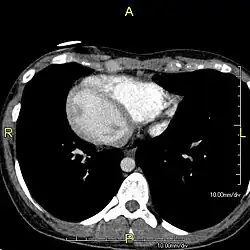

Situs inversus (lat. invertierte Lage) ist der medizinische Ausdruck für das Vollbild einer Heterotaxie, eine seltene, an sich nicht krankhafte Besonderheit der Anatomie, bei der sich die einzelnen Organe spiegelverkehrt jeweils auf der anderen Seite des Körpers befinden. Das Antonym ist der Situs solitus, also die normgerechte Position der Organe im Körper.[1] Synonyme des Situs inversus sind: Inversio viscerum,[2] Situs inversus viscerum, Situs inversus totalis, Situs perversus, Situs transversus, Situs rarior,[3] Situs transversus viscerum,[4] Situs oppositus, Situs inversus completus.

Beim Situs inversus partialis sind nur entweder die Thoraxorgane (also die Herzhälften und die Lungenflügel) oder die Bauchorgane spiegelbildlich quer vertauscht. Beim Situs inversus incompletus besteht keine Dextrokardie. Beim seltenen Situs inversus viscerum specularis ist nur einer von beiden eineiigen Zwillingen betroffen.[5]

Entsprechend der spiegelverkehrten Lage des Herzens (Dextrokardie, gr. dexios = „rechts“, kardia = „Herz“) müssen die Ableitungen des EKGs angepasst werden; es müssen u. a. in den Brustwandableitungen die Elektroden spiegelbildlich zu Situs-solitus-Patienten am Brustkorb befestigt werden.[8][9][10] Differentialdiagnostisch muss an Verpolungen gedacht werden.[11] Bei einigen Menschen mit Pätau-Syndrom (Trisomie 13) liegt eine Dextrokardie vor, während die übrigen Organe wie üblich angelegt sind. Diese spiegelbildliche Rechtsverlagerung nur des Herzens heißt auch Situs inversus cordis.[12][13] In der Kardiologie unterscheidet man fünf verschiedene Formen einer Malposition des Herzens: Dextrokardie beim Situs solitus, Lävokardie beim Situs inversus, eine Mesokardie mit mittelständigem Herz, eine Dextroposition oder eine Lävoposition bei extrakardialer Ursache und eine Ectopia cordis. Auch ist beim Betrachten eines Röntgen-Thorax-Bildes an eine Dextrokardie oder an eine Rechts-links-Verwechslung zu denken.